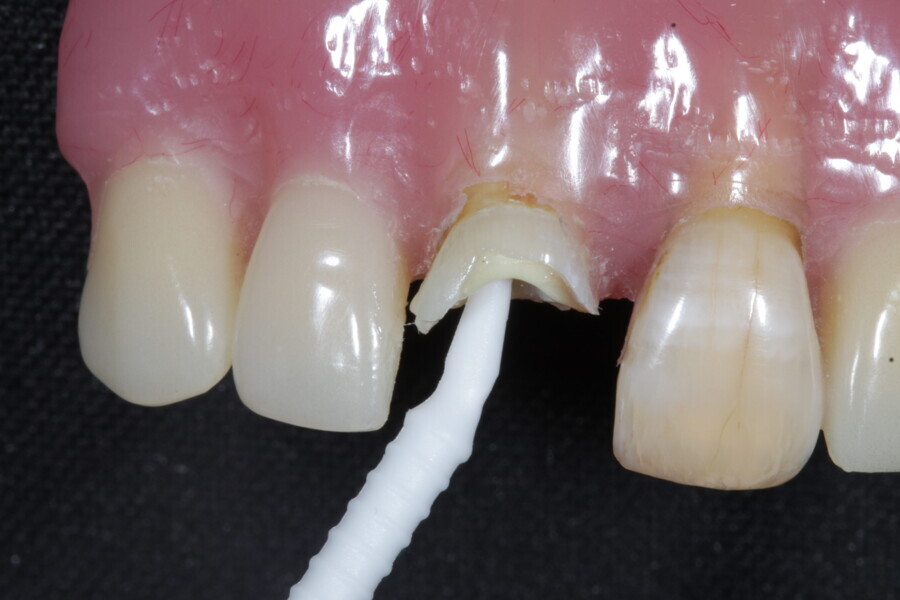

1. functional and aesthetic reconstruction of a maxillary anterior tooth using fibre-reinforced flexible micro-posts after endodontic treatment (Figs. 3–20);

Example 1—showing functional and aesthetic reconstruction of a maxillary anterior tooth using fibre-reinforced flexible micro-posts after endodontic treatment.